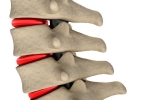

髋关节由髋臼和股骨头构成,髋臼为骨盆外侧的半球形凹陷,股骨头则是大腿骨顶端的球形结构。该关节被关节囊包裹,周围有髂股韧带、耻股韧带等多条韧带加固,内部存在盂唇结构以增加稳定性。从体表定位来看,髋关节大致位于腹股沟中点向大腿外侧延伸的区域,站立时髂前上棘与耻骨联合连线的中点可触及关节前侧。髋关节属于杵臼关节,具有屈伸、内收外展、旋转等多轴向运动功能,日常行走、跑步、下蹲等动作均依赖其活动。由于长期负重和活动磨损,中老年人易出现髋关节骨关节炎、股骨头坏死等病变,表现为腹股沟区疼痛和活动受限。